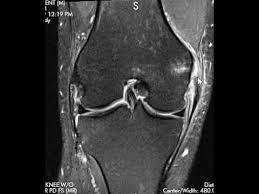

Medial collateral ligament (mcl) injuries are graded into three groups on mri, much in the same way as many other ligaments:.

Mild sprain with ligaments stretched but not torn. Injuries to the medial collateral ligament most often happen when the knee is hit directly on its outer side. Grade i is sprained, grade ii is a partial tear, grade iii is a complete tear of the ligament. 3 online classroom games to energize your class; A grade 1 (minor) mcl tear can take from a few days to a week and a half to heal enough for a return to normal activities, including sports. Case discussion typical findings of a grade 2 medial collateral ligament (mcl) injury with associated posteromedial corner injury. A medial collateral knee ligament sprain or mcl sprain is a tear of the ligament on the inside of the knee. Knee sprains and meniscal injuries.

Medial collateral ligament (mcl) injuries. Grade 2 mcl sprain some of the ligaments are torn in this grade of injury. Severe sprain with complete tear of ligaments. Although the knee joint may not hurt or swell very much, a mild ligament sprain can increase a repeat injury risk. (severe sprain or partial tear) high signal is seen medial to the ligament, with high signal or partial disruption of the ligament A medial collateral knee ligament sprain or mcl sprain is a tear of the ligament on the inside of the knee. Crutches and restricted weight bearing This usually causes some instability in your knee joint. Treatment is usually bracing unless there is gross varus instability in which case repair or reconstruction is performed. Medial collateral ligament (mcl) injuries are graded into three groups on mri, much in the same way as many other ligaments:. Hold for about 6 seconds, then lower slowly. 3 online classroom games to energize your class; Knee ligament sprains are graded in severity from one to three: